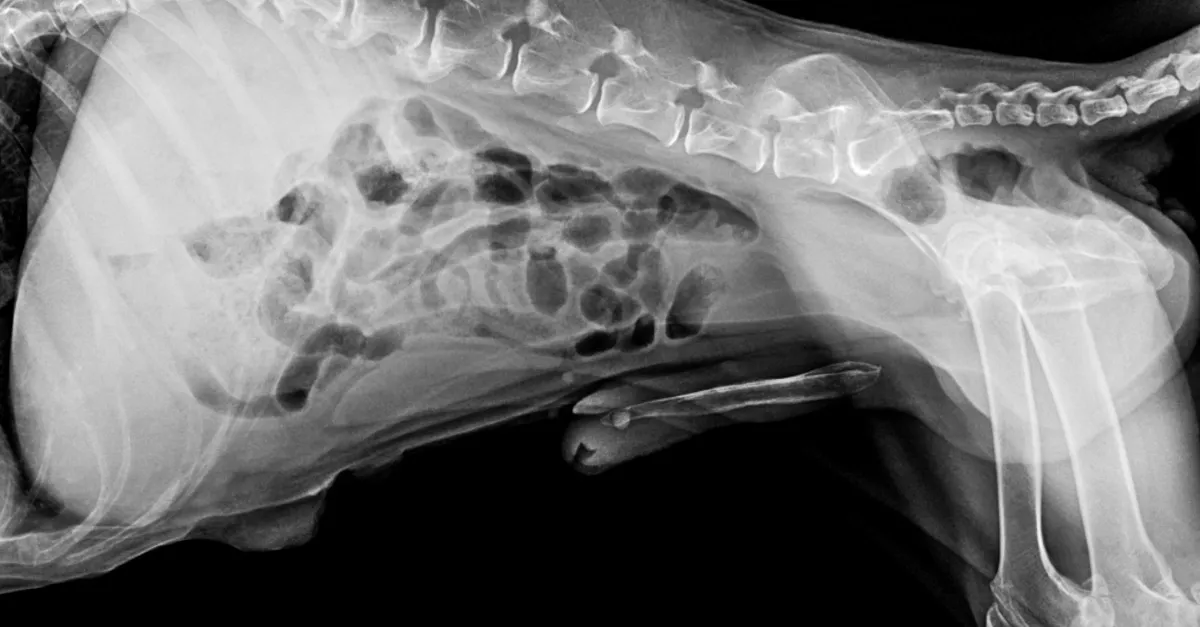

A röntgenvizsgálat nemcsak azt mutatta ki, hogy a kutya csípőízületi diszpláziában és ízületi gyulladásban szenved, hanem azt is, hogy több aggasztó idegen test volt a csípőjében, a gerinc közelében.

Mint kiderült, egy nagy és több kisebb golyó volt a kutya testében. A jelek szerint Momót még az örökbefogadása előtt lelőtték. „Eléggé megdöbbentem és elszomorodtam” - mondta a gazdája. Bár az állatorvos biztos benne, hogy az idegen tárgyak, amelyek valószínűleg egy sörétes puskából származnak, nem okoztak fájdalmat, a golyók majdnem megölték. Az egyik nagyobb golyó nem sokkal a gerince mellett állt meg.